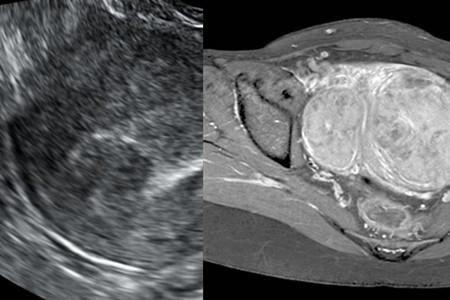

子宫肌瘤是女性会患上的一种肿瘤,这种肿瘤大多数是良性,大家不必害怕。子宫肌瘤就是在女性生殖器官里面的一个肿瘤,我们只需要通过正常的手术将肿瘤切除,然后根据医生的叮嘱,就可以恢复健康。但是手术有利也有弊,它可以让我们恢复健康,但是子宫肌瘤手术也是有一定的后遗症。